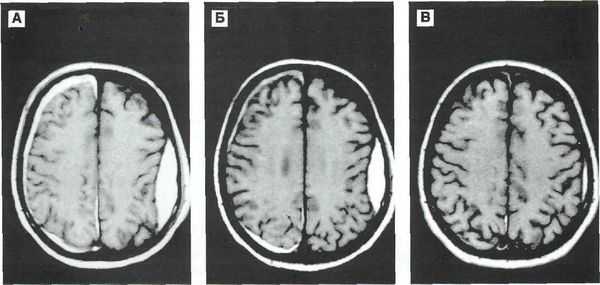

Механизмы вторичного повреждения нейронов при тяжелой черепно-мозговой травме (часть 1)

Обзор посвящен механизмам вторичного гипоксически-ишемического повреждения головного мозга при тяжелой черепно-мозговой травме. Приводятся новые данные по механизмам глутамат-кальциевого повреждения нейронов и ок-сидантного стресса. Ключевые слова: центральная нервная система, черепно-мозговая травма, гипоксия, ишемия, глутамат-кальциевый каскад, оксидантный стресс.